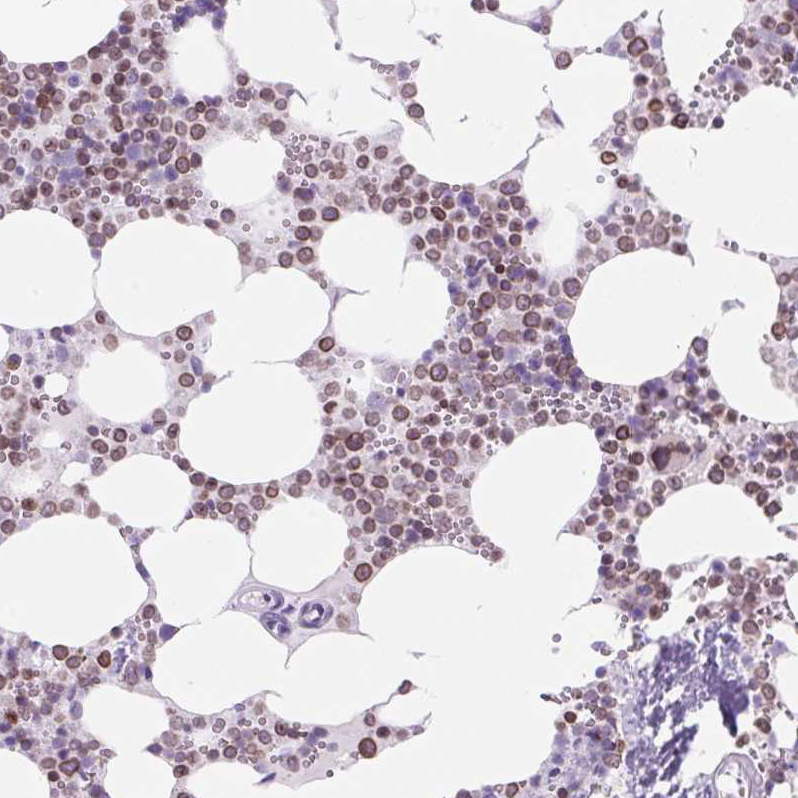

Immunohistochemical staining of human bone marrow shows moderate nuclear positivity in hematopoietic cells.